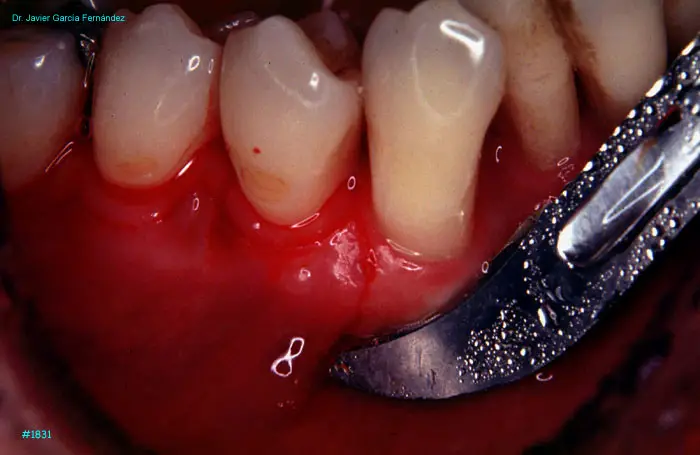

image 97